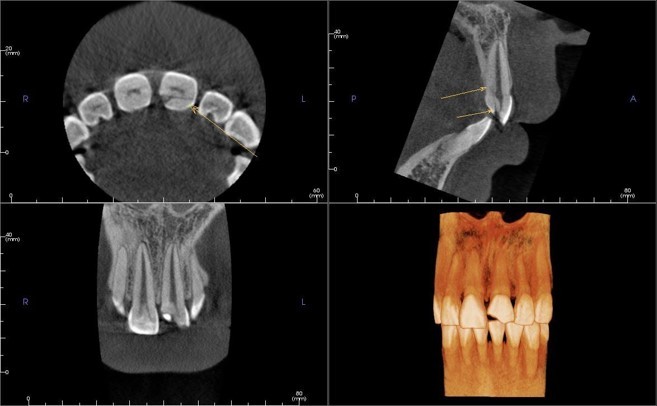

95Пациент 65 лет обратился за комплексной стоматологической реабилитацией с жалобами на отсутствие зубов и эстетическую неудовлетворенность. Пациент долгое время не обращался за стоматологической помощью, вследствие чего были утеряны зубы на верхней и нижней челюсти. В полости рта наблюдаются пародонтальных патологии имеющихся зубов, зубоальвеолярное изменение в виде феномена Попова – Годона (рис 1,2,3.) На панорамной рентгенограмме […]